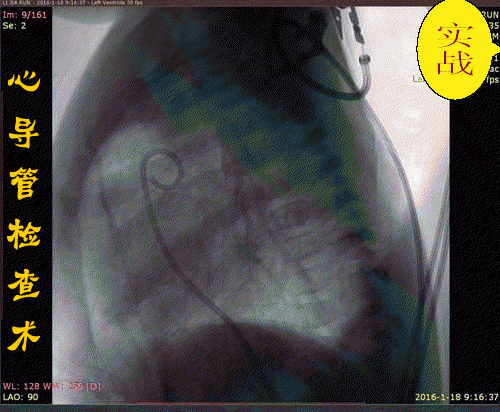

心导管检查术是将特制的、有一定韧度的不透X线的导管,经外周动、静脉送入心脏和大血管指定部位,用以诊断心血管疾病的一种常用介入性诊断技术。可明确诊断心脏和大血管病变的部位与性质、血流动力学改变及程度,为采用介入性治疗或外科手术治疗提供依据。

2.配合医生穿刺:一般采用Seldingers经皮穿刺法。病人取仰卧位,局麻后﹙儿童采用全身麻醉﹚在严格的无菌操作下自股静脉、上肢贵要静脉、锁骨下静脉$2右心导管术$3或股动脉、肱动脉$2左心导管术$3插入导管到达相应部位。整个检查均在X线透视下进行,并作连续的心电和压力监测。动脉穿刺成功后注入肝素3000U,随后操作每延长lh追加肝素1000U。